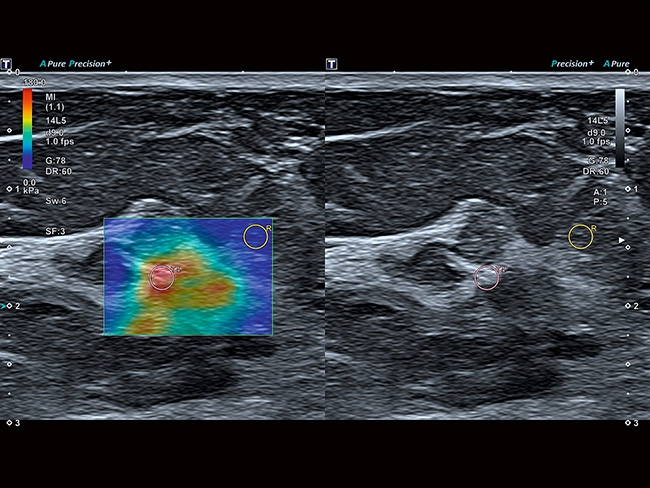

• SMI. Опция, упрощающая визуализацию микроциркуляторного русла. С ее помощью обследуются сосуды с низкой интенсивностью кровотока, изучаются наиболее тонкие структуры. SMI упрощает диагностику новообразований, минимизирует вероятность ошибки.

Эластография:

Компрессионная, Сдвиговая

Эластография сдвиговой волной/Эластометрия:

Нет

Компрессионная эластография: